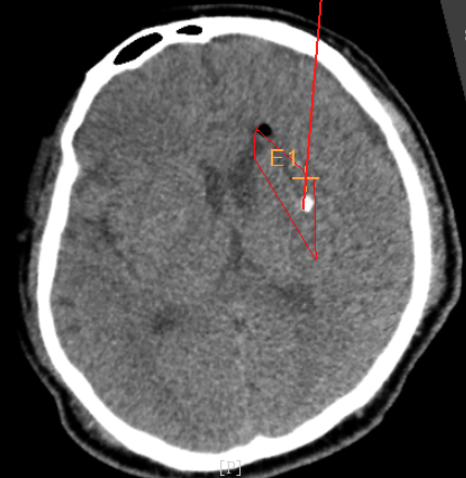

3個(gè)月前CT:腦出血

alt text

術(shù)前CT:血腫已經(jīng)液化,但仍有占位效應(yīng)